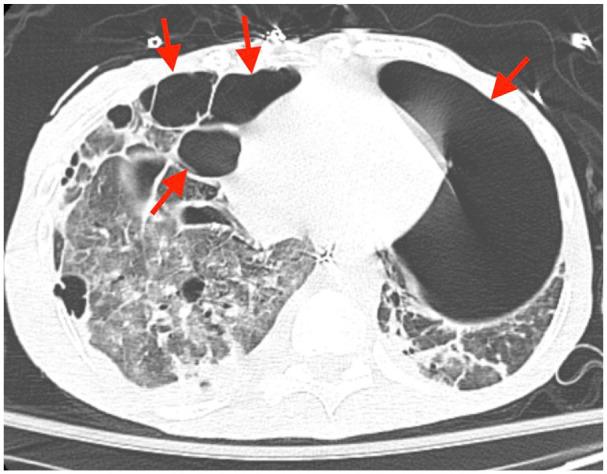

Patients with a history of drug abuse and right-sided endocarditis are particularly susceptible to developing septic pulmonary emboli. Rarely, septic pulmonary emboli can cause severe lung injury resulting in parenchymal loss despite appropriate antibiotic therapy. We present 2 cases of severe lung injury associated with septic pulmonary emboli stemming from right-sided infective endocarditis, emphasizing 2 rare complications: bilateral spontaneous pneumothorax and pneumatocele formation.

Abstract Image